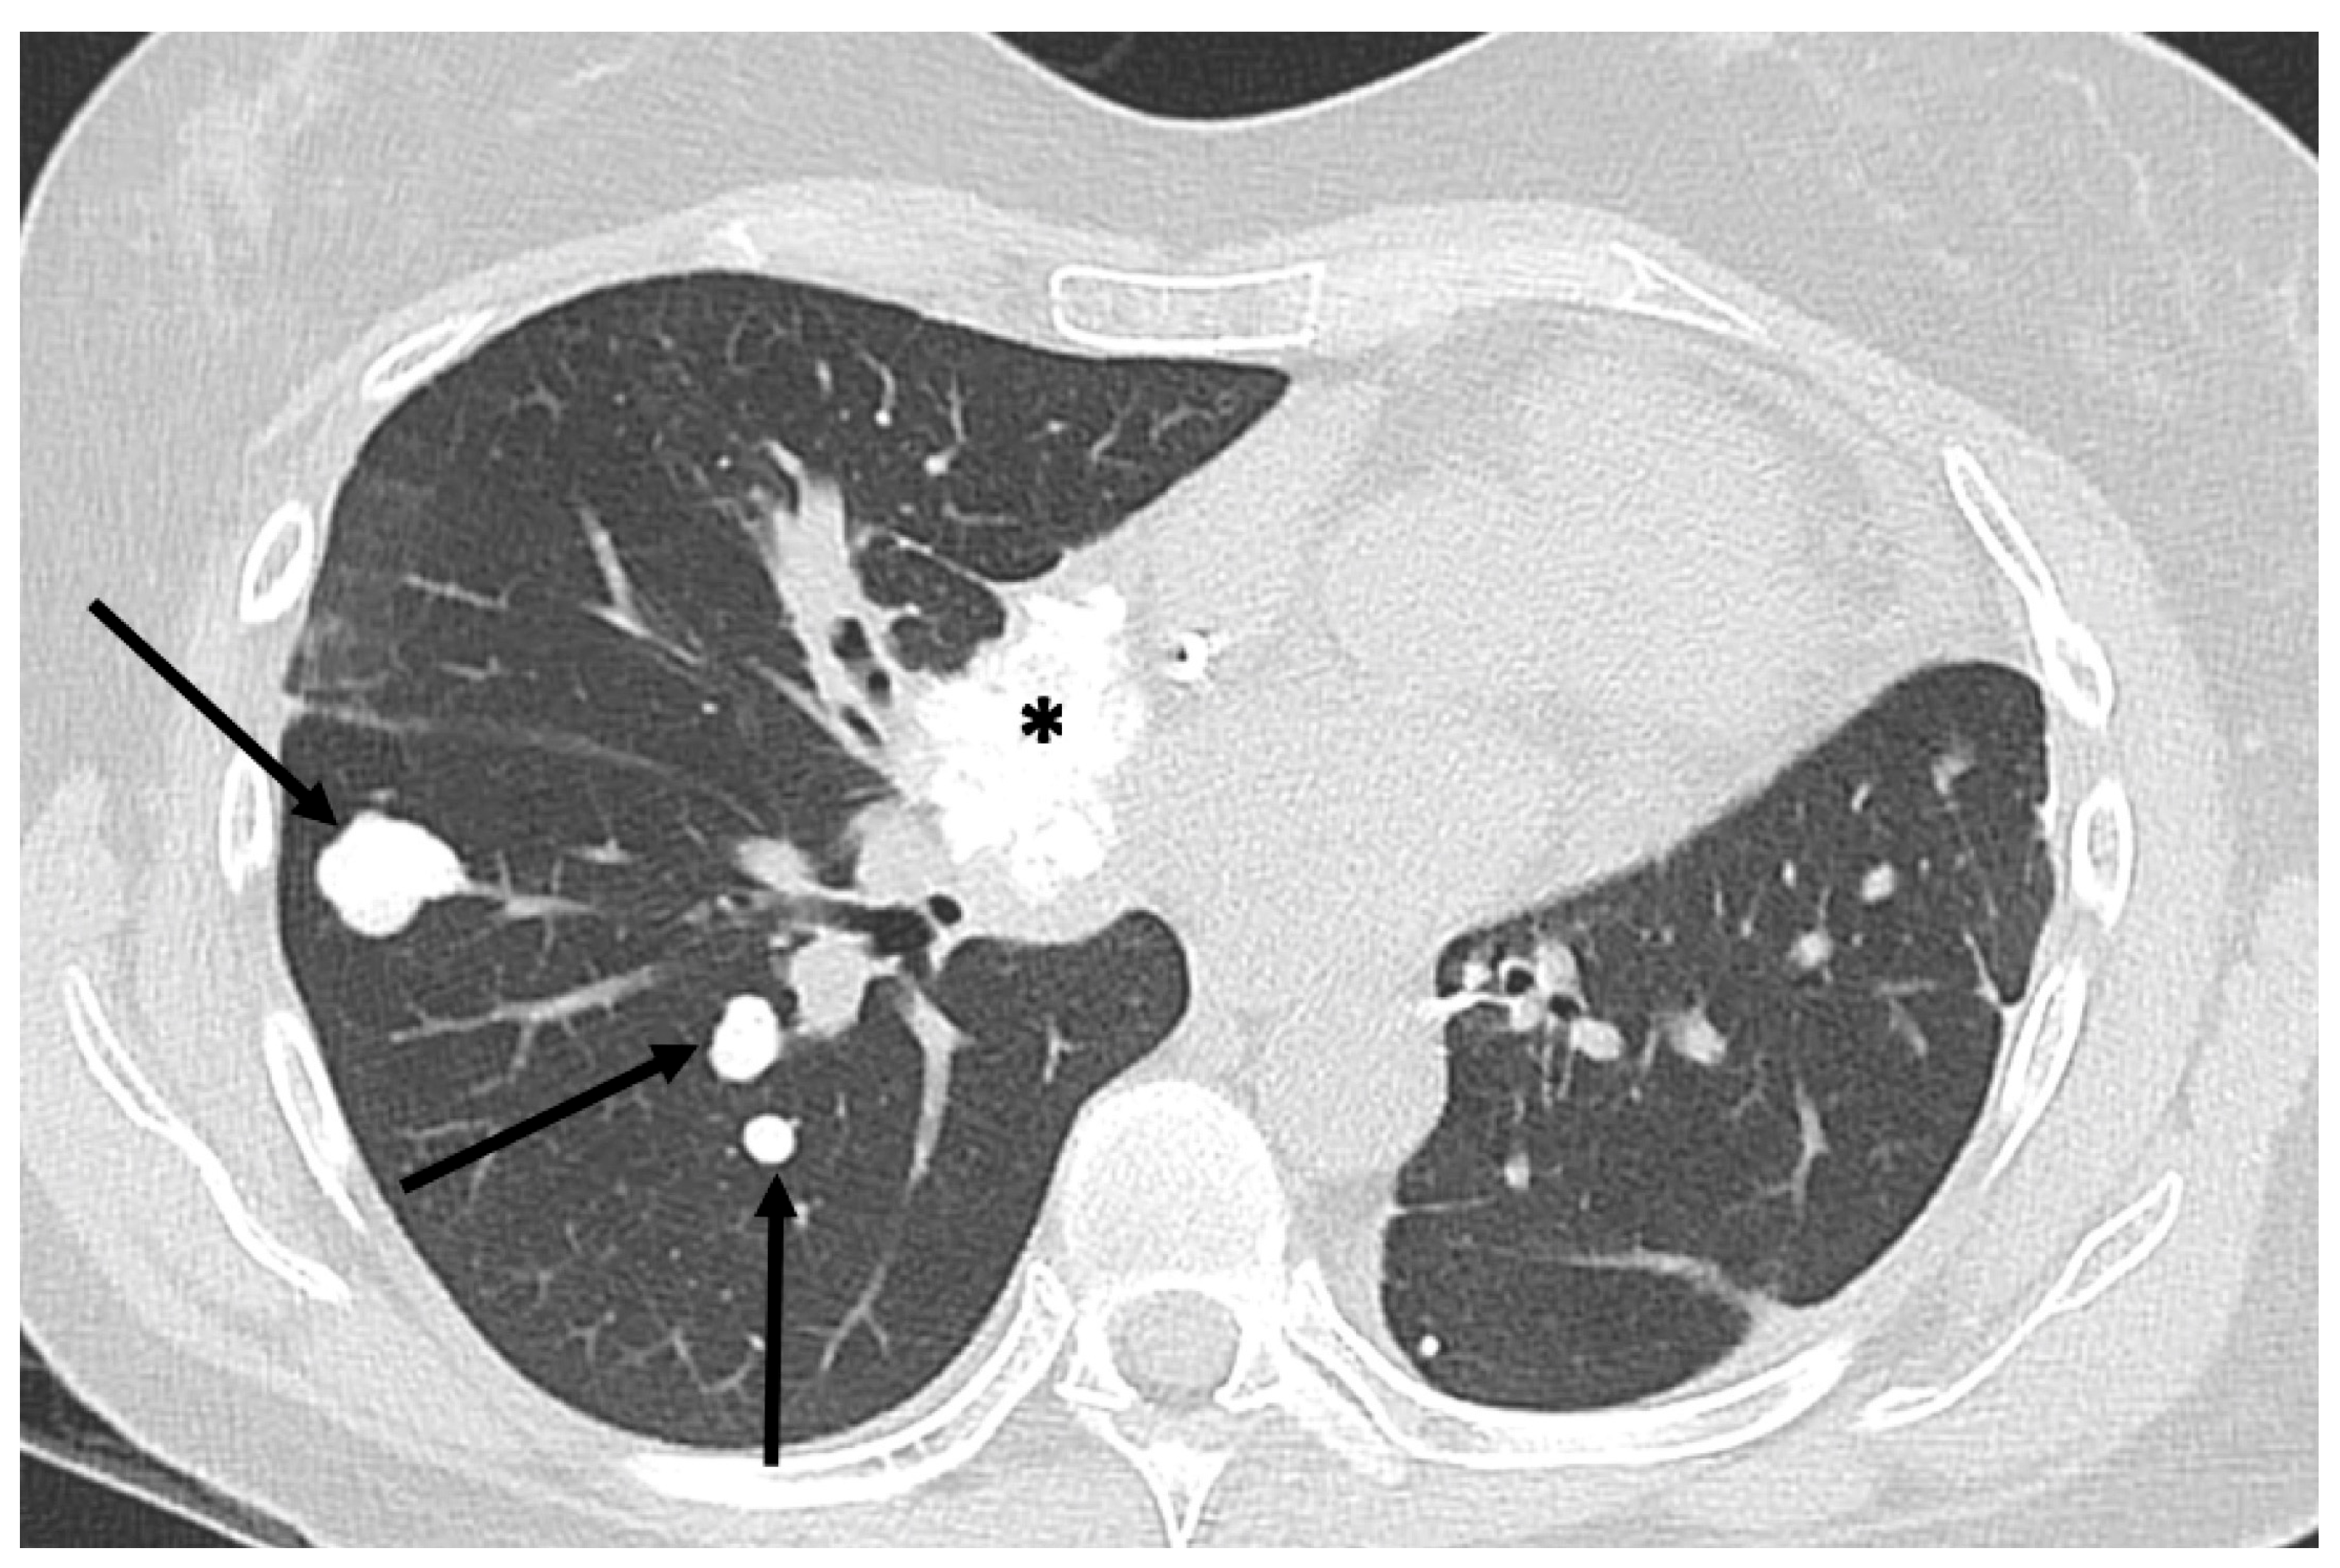

3. Metastatic Patterns of Osteosarcoma

- Chiesa, A.M.; Spinnato, P.; Miceli, M.; Facchini, G. Radiologic Assessment of Osteosarcoma Lung Metastases: State of the Art and Recent Advances. Cells 2021, 10, 553. [Google Scholar] [CrossRef] [PubMed] [PubMed Central]

- Brader, P.; Abramson, S.J.; Price, A.P.; Ishill, N.M.; Emily, Z.C.; Moskowitz, C.S.; La Quaglia, M.P.; Ginsberg, M.S. Do characteristics of pulmonary nodules on computed tomography in children with known osteosarcoma help distinguish whether the nodules are malignant or benign? J. Pediatr. Surg. 2011, 46, 729–735. [Google Scholar] [CrossRef] [PubMed] [PubMed Central]

- Ghosh, K.M.; Lee, L.H.; Beckingsale, T.B.; Gerrand, C.H.; Rankin, K.S. Indeterminate nodules in osteosarcoma: What’s the follow-up? Br. J. Cancer 2018, 118, 634–638. [Google Scholar] [CrossRef] [PubMed] [PubMed Central]

- Ciccarese, F.; Bazzocchi, A.; Ciminari, R.; Righi, A.; Rocca, M.; Rimondi, E.; Picci, P.; Bacchi Reggiani, M.L.; Albisinni, U.; Zompatori, M.; et al. The many faces of pulmonary metastases of osteosarcoma: Retrospective study on 283 lesions submitted to surgery. Eur. J. Radiol. 2015, 84, 2679–2685. [Google Scholar] [CrossRef] [PubMed]